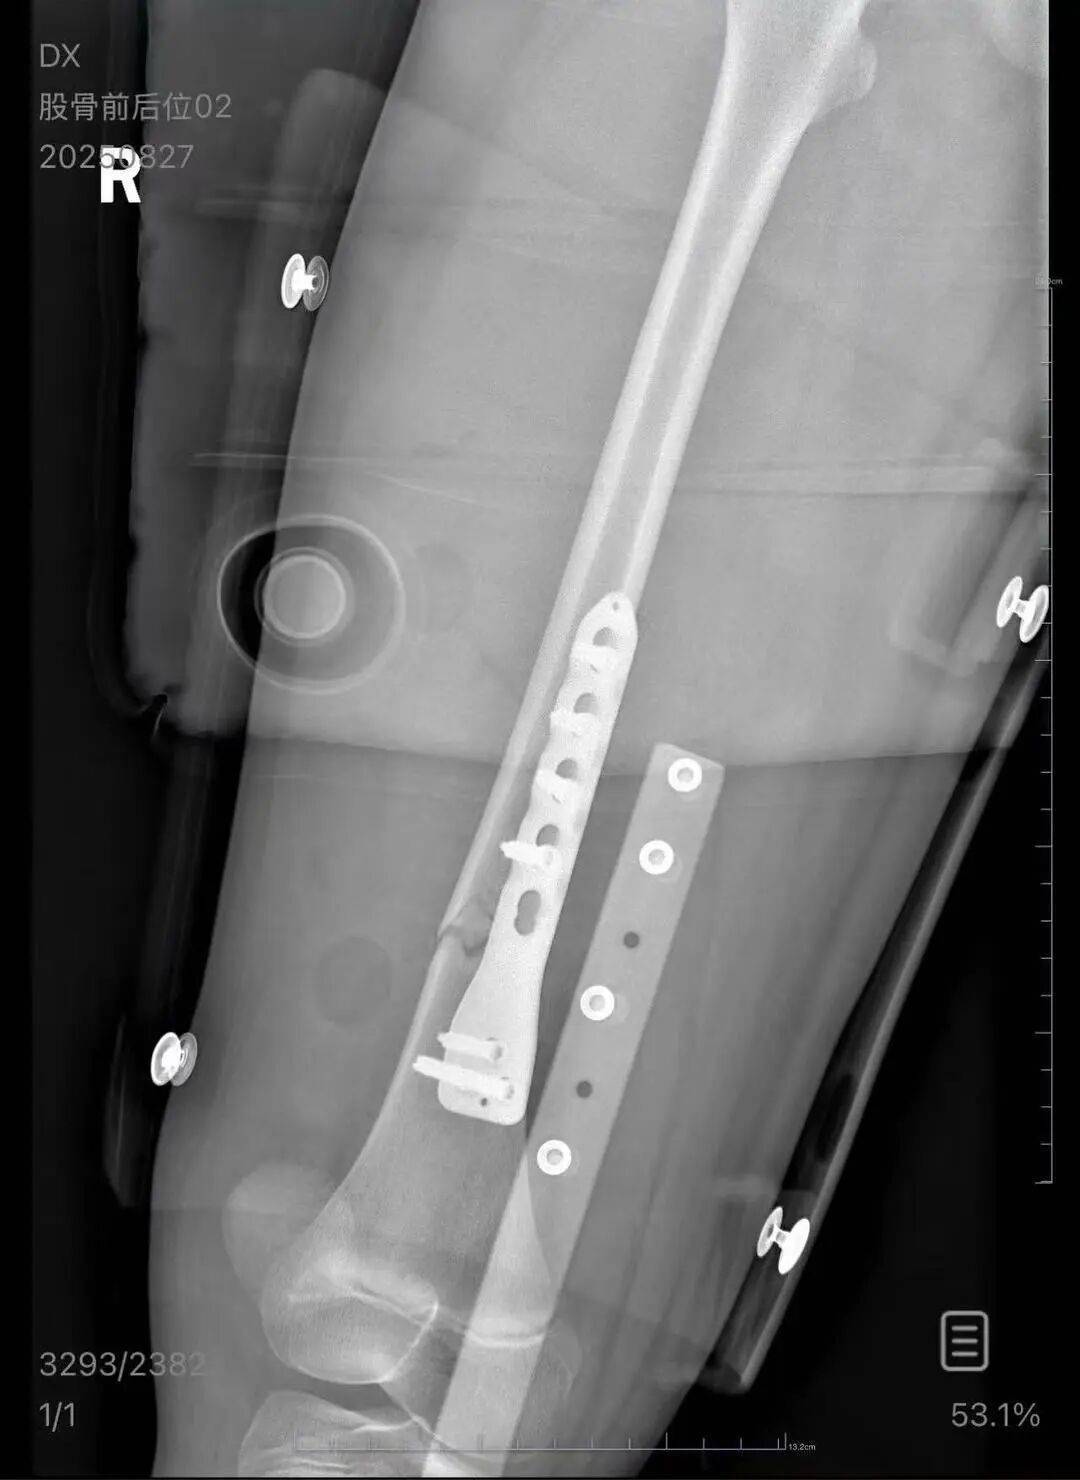

▲朱女士女儿手术后拍的X光片 受访者供图

朱女士向记者出示的医院病历显示,8月24日凌晨,朱女士的女儿到医院就诊理财风险。医院诊断朱女士的女儿右股骨骨折,需要住院进一步治疗。